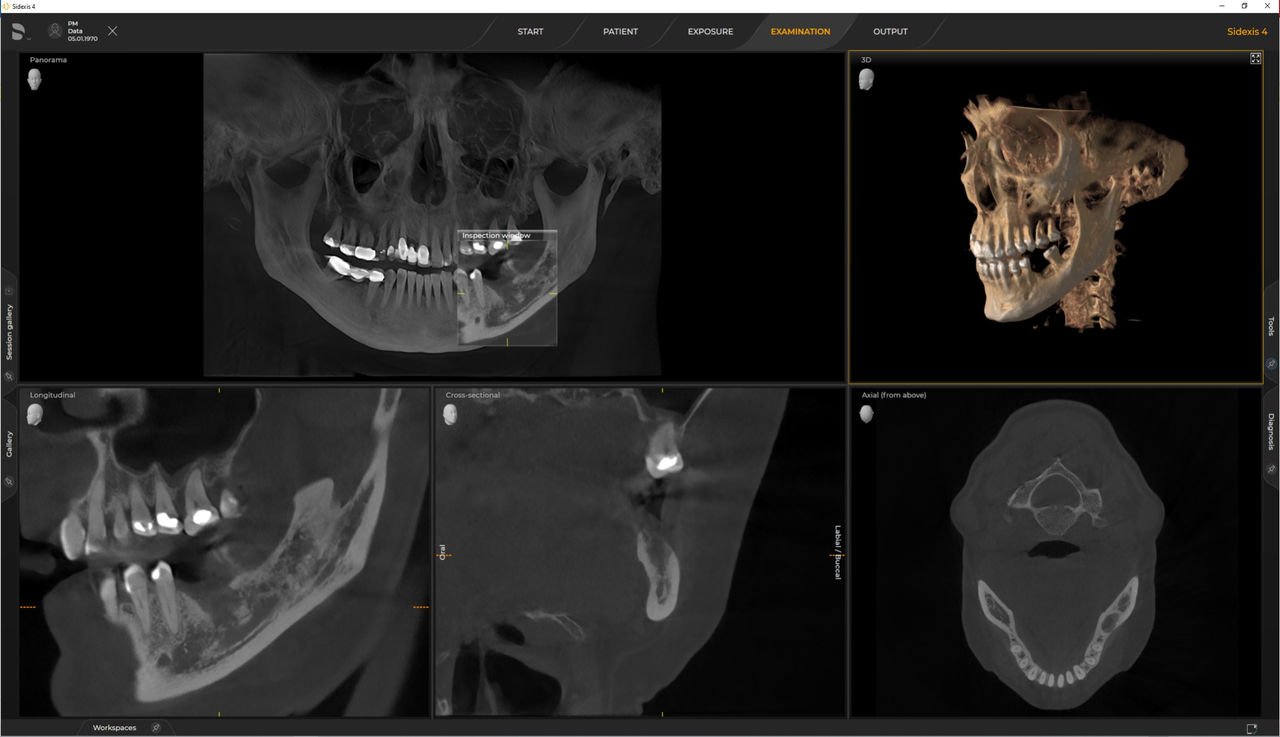

Los requisitos siguen aquellos del software de procesamiento de imágenes de Sidexis 4 y Axeos. Para obtener más detalles, consulte los requisitos del sistema Sidexis 4 y los requisitos de instalación de Axeos.

Las unidades 3D de Dentsply Sirona funcionan exclusivamente con Sidexis 4. Sin embargo, la migración de datos de Sidexis XG a Sidexis 4 es muy fácil. Sidexis 4 permite una experiencia digital completa con las últimas herramientas.